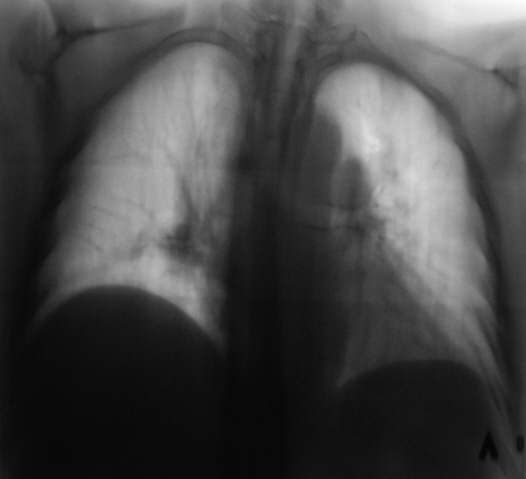

Картина ампутации левого нижнедолевого бронха, ателектаз нижней доли слева, диссеминация метастатической природы

Левый главный бронх оттеснен кверху, по всей видимости, за счет увеличения л/узлов бифуркационной группы?

Теперь о данном наблюдении. Оценка рентгенограмм к сожалению очень индивидуальный и субъективный процесс. Ход моих мыслей: пожилой пациент без жалоб, а на снимках выраженная диффузная патология в грудной клетке - сразу включается механизм перехода мышления на онкологические рельсы. Я много лет работал в детской торакальной хирургии, поэтому так насторожен и "кидаюсь" на малейшие смещения средостения - мне показалось, что есть смещение сердца влево. Конечно, лучше, чтобы снимок был чуть более жестким, и на нем не было бы абсолютно непрозрачных мест, но что имеем...

Внутри тени сердца, параллельно контуру левого желудочка внизу есть дополнительный контур, который я расценил как наружную границу уменьшенной левой нижней доли, отсюда и все мои последующие выводы. Именно эти места уже отмечены Вами желтыми стрелками - просто наши оценки одного и того же различаются. Насчет четкой видимости ампутации бронха - согласен, двоечтение возможно.

В литературе и на практике встречал 3 основных варианта картины ателектаза нижней доли слева. Для всех них в прямой проекции характерно легкое смешение сердца влево, повление интенсивной треугольной тени за сердцем слева медиально, второго контура за сердцем. Но в боковой проекции картина разнообразна (в какой плоскости преимущесвенно сложится доля - как веер) и сводится к трем основным вариантам:

В отличии от уважаемых коллег, я не увидел признаков ателектаза ни слева, ни справа, при этом согласен с наличием диффузных изменений, в сочетании с увеличением лимфоузлов в обоих корнях. Диф. ряд весьма широк.